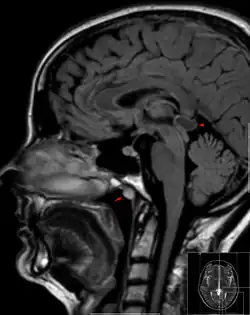

Tornwaldt cyst imaged on sagittal MRI (FLAIR). The cyst appears hyperintense in the midline of the nasopharynx (arrow). In this case there is also a cyst of the pinealis gland (arrowhead) showing a signal intensity slightly higher than the CSF.

A Tornwaldt cyst (also spelt as Thornwaldt or Thornwald[1]) is a benign cyst located in the upper posterior nasopharynx. It was first described by Gustav Ludwig Tornwaldt. It can be seen on computed tomography (CT) or magnetic resonance imaging (MRI) of the head as a well-circumscribed round mass lying in the midline. In most cases, treatment is not necessary. Indications for treatment include symptomatic lesions, large lesions (>1 cm), or lesions adjacent to the eustachian tube orifice.[2]